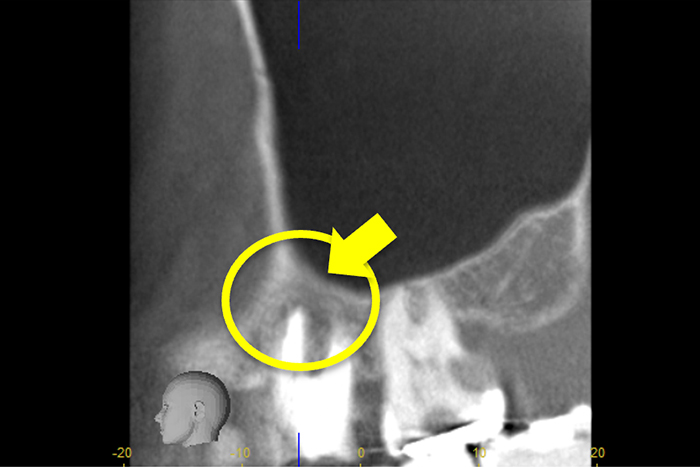

根の横に誤った穴をあけてしまい、気づかずに薬を入れてしまっている。また、器具が破折し、根の先に飛び出ている。

精密根管治療治療終了時歯の側面の穴と根尖はMTAにより緊密に封鎖した。